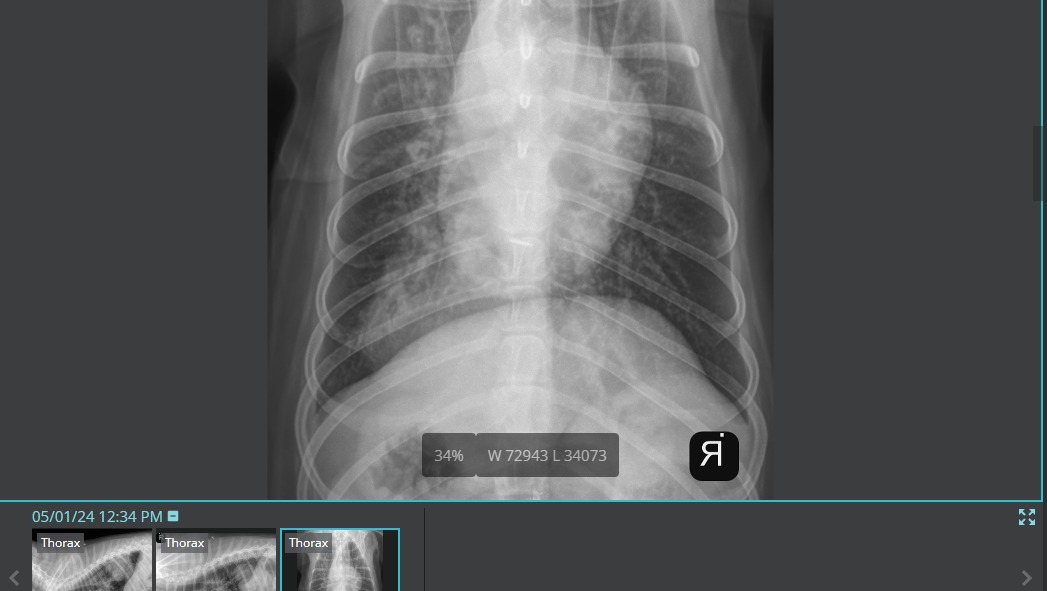

I was out of town for work for 11 days and picked Chewie up from his dog sitter this past Wednesday (5/1). He was extremely low energy and had a dry cough. I rushed him to the ER thinking he had pneumonia. After taking radiographs, we discovered that he has a very large tumor in his left lung. This tumor is so large that it is making it extremely difficult for Chewie to breathe, eat, go potty, and get comfortable resting.

This is an extremely aggressive cancer. He went from presenting zero symptoms to lethargy and trouble breathing within weeks. After lots of tests at the emergency vet, it was determined that Chewie only has the one isolated mass in his lung - that there are no other cancers present and all other organs are functioning normally.

Because the cancer is isolated to his left lung and his other organs still have full function, Chewie is a great candidate for a Lung Lobectomy - which will give him the chance for a full recovery, and give him several more years on this earth with us.